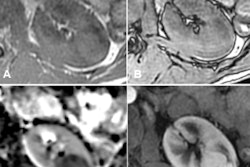

The biggest change is that the association has revised the role of multiparametric MRI (mpMRI) in the diagnosis of prostate cancer. Key changes include the following:

- Adhere to Prostate Imaging Reporting and Data System (PI-RADS) guidelines for mpMRI acquisition and interpretation.